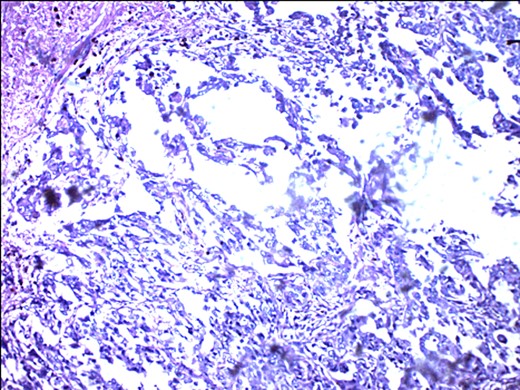

PR-negative immunohistochemistry typing with rabbit progesterone antibodies.

S-100 cytoplasmic positivity in keeping with melanocytic differentiation. Immunohistochemistry.